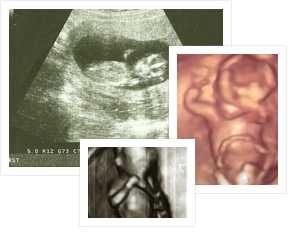

Фото УЗИ плода на 11 неделе беременности

Предлагаем вашему вниманию несколько вариантов УЗИ.

11 недель беременности 3D УЗИ

11 неделя беременности фото УЗИ живота

11 неделя беременности

Голова плода на УЗИ беременности в 11 недель

Диафрагмальная грыжа (стрелка), беременность 11 недель

УЗИ 11 недель

Фото УЗИ и животиков на 11 недели беременности: